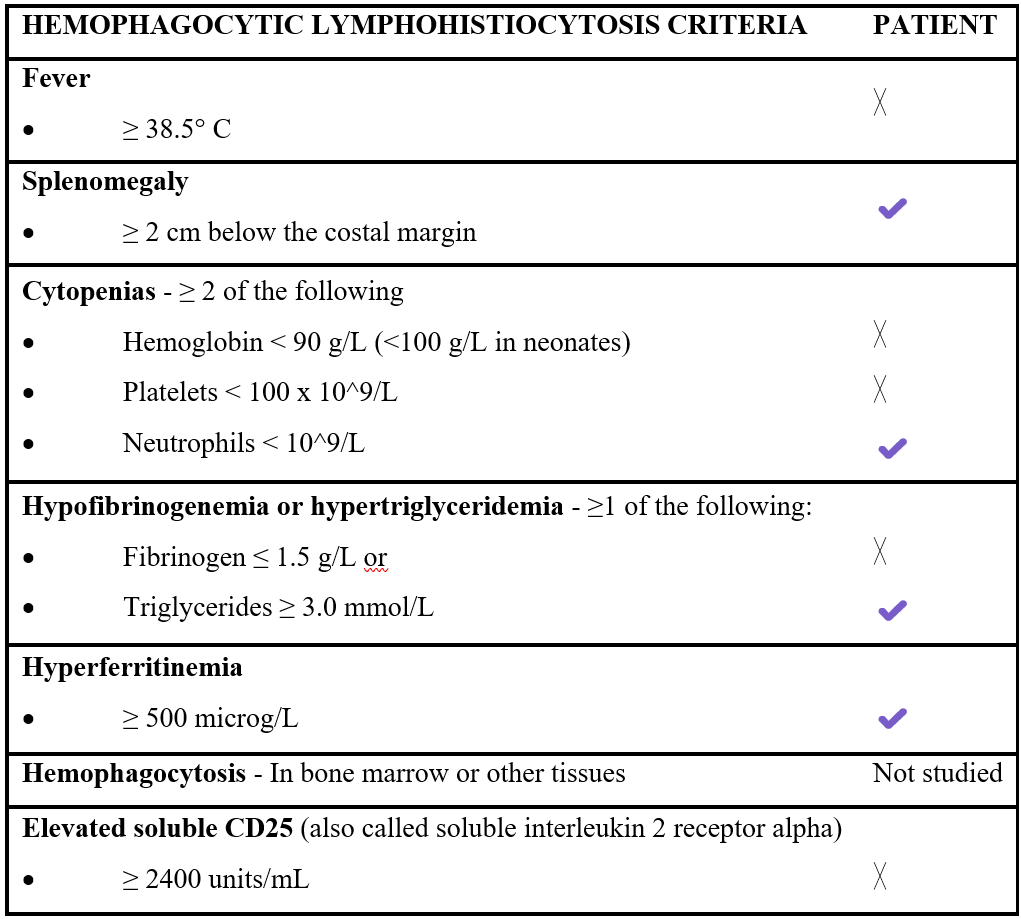

Table 2: Hemophagocytic lymphohistiocytosis criteria 2024 (HLH-24) and which of them does our patient fulfill.

Diagnosis of non-familial HLH relies on the HLH-2024 criteria, with ≥5 fulfilled items required of the following: fever, splenomegaly, cytopenias in at least two lineages, hypofibrinogenemia or hypertriglyceridemia, hyperferritinemia, haemophagocytosis in bone marrow or other tissues and elevated sCD25 (Table 2). However, these criteria were originally designed for paediatric populations with more florid presentations and which may not fully capture the subtle or evolving forms of HLH seen in adults. In this context, the H-Score offers an alternative tool incorporating variables and threshold values more applicable to adult patients. Nevertheless, both systems have limitations and clinical judgement remains essential, particularly when HLH is suspected but the patient does not fulfil complete criteria [1,4].

Our patient exemplifies this scenario. She fulfilled three of HLH-2024 criteria (splenomegaly, hypertriglyceridemia and hyperferritinemia), along with cytopenias and elevated sCD25. Although she did not meet the five-criteria requirement, the constellation of findings, clinical trajectory and absence of alternative explanations strongly suggested an HLH-like hyperinflammatory syndrome. The unique features of our case highlights how strict adherence to classical criteria may delay diagnosis in adults and supports the need for flexible diagnostic strategies, especially in the context of identifiable triggers [4,7].